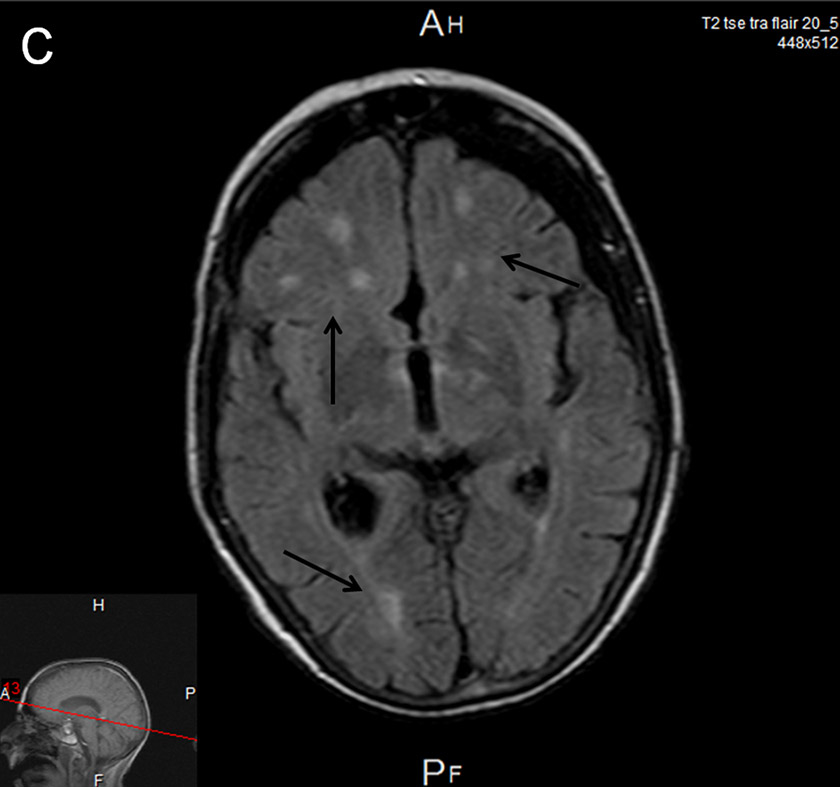

Cerebral MRI.

C Axial FLAIR image: Areas of ischaemia in the subcortical anterior and posterior territories.

Two days later the patient became drowsy again with signs of upper brainstem dysfunction. Cerebral MRI showed meningeal enhancement and widespread punctate ischaemic-type lesions affecting vascular beds of both carotid and vertebral arteries bilaterally (fig. 1 A–C). MR angiography showed numerous irregularities of the distal arteries, suggestive of vasculitis (fig. 1D). Antibiotic treatment was broadened to include meropenem 3 × 2 g and dexamethasone was restarted but brainstem dysfunction did not improve. Supportive treatment was withdrawn and the patient died on day 21 post-surgery. Subsequent CSF cultures were sterile.